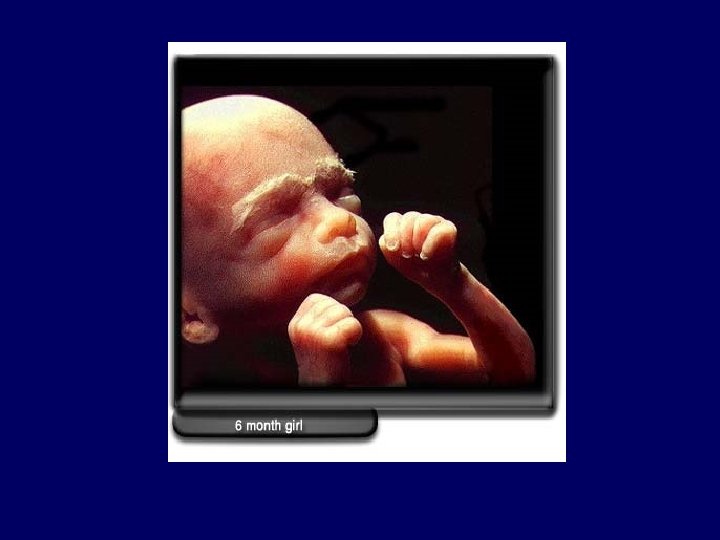

Fetal period • Fetus less susceptible to teratogens but still susceptible to toxicity and behavioral teratogenicity • Some agents paradoxically cause more problems in 2 nd trimester than in 1 st: Varicella

Fetal period Birth defects: Oligohydramnios: NSAIDS ACE inhibitors Hypotension/ Cardiac arrhythmia/ Ischemia: Cocaine, phenytoin, anti-arrhythmics